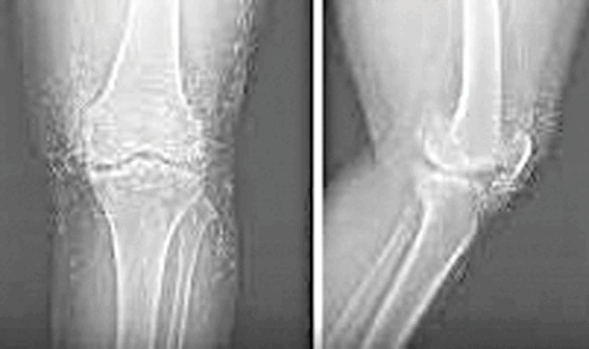

Doctors in South Korea found hundreds of pure gold threads in the knees of a 65-year-old woman treated for osteoarthritis.

She had turned to gold thread acupuncture after painkillers, anti-inflammatory and steroid injections failed to help. The alternative procedure, meant to relieve pain, only worsened her condition as she increased her visits to several times a week.

X-rays later revealed not just osteoarthritis damage, but countless gold threads embedded in her knee tissue. Doctors warn that the treatment has no proven benefits and carries serious risks, including cysts, tissue damage and complications during MRI scans.